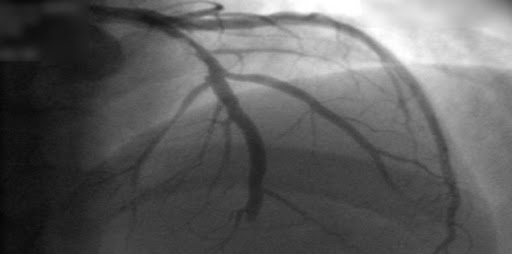

En este análisis (ya previsto en el protocolo del ensayo REVIVED-BCIS2)se  encontró que las pruebas de viabilidad miocárdica no identifican a los pacientes con miocardiopatía isquémica que se benefician de la intervención coronaria transcutánea. La extensión del miocardio no viable, pero no la extensión del miocardio viable, se asocia con la supervivencia libre de eventos y la probabilidad de mejora de la función ventricular izquierda. JAMA Cardiology, 25 de octubre de 2023.